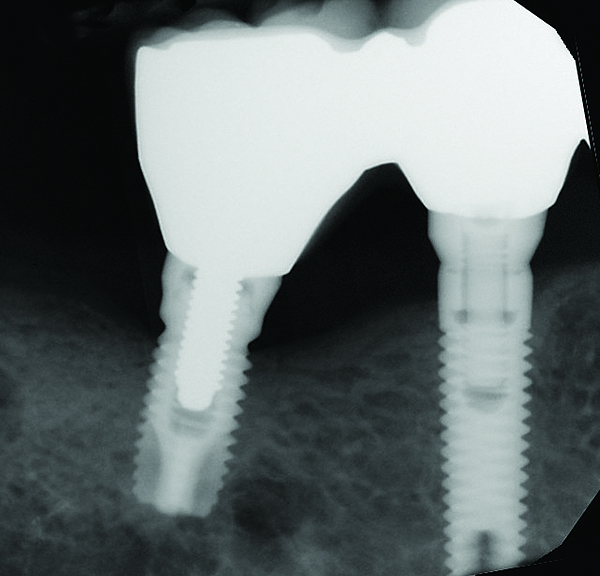

During the first year after implantation, patients with completely restored edentulous ridges demonstrated a mean total bone loss ranging from 0.90 mm to 1.64 mm.58-60 After the first year, the mean annual rate of bone resorption ranged from 0 mm to 0.15 mm58-65 (Figure 1 through Figure 14).

Fig 1 through Fig 6. Periapical radiographs of a 52-year-old man who received a fixed porcelain-fused-to-metal reconstruction supported by abutments attached to externally hexed dental implants. Fig 1 through Fig 3 are at initial prosthesis placement: maxillary right (Fig 1), textured surfaced threaded titanium implants at site Nos. 2, 4, and 6; maxillary anterior (Fig 2), implants at site Nos. 7 through 9; maxillary left (Fig 3), implants at site Nos. 12 and 14. Fig 4 through Fig 6 are 10 years post-insertion of the prosthesis: maxillary right (Fig 4), maxillary anterior (Fig 5), and maxillary left (Fig 6). Note minimal to no bone loss radiographically around the implants 10 years post-insertion of prosthesis.

Figure 5

Fig 7 through Fig 14. Periapical radiographs of a 62-year-old woman who received a fixed porcelain-fused-to-metal reconstruction supported by abutments by internally connected dental implants. Fig 7 through Fig 10 are at initial prosthesis placement: mandibular site Nos. 30 and 29 (Fig 7); mandibular site Nos. 26, 25, and 23 (Fig 8); mandibular site Nos. 23 and 21 (Fig 9); mandibular site Nos. 21 through 19 (Fig 10). Fig 11 through Fig 14 are 11 years later (2013) and show excellent preservation of the vertical bone levels around the implants: mandibular site Nos. 30 and 29 (Fig 11); mandibular site Nos. 26 and 25 (Fig 12); mandibular site Nos. 25 and 23 (Fig 13); mandibular site Nos. 20 and 19 (Fig 14). It is interesting to note that in the mandibular right posterior quadrant there is a matched pair, ie, an external hex dental implant (No. 30) adjacent to an internally connected dental implant (No. 29). The bone levels around each of these designs are well-preserved at the 11-year follow-up.

Figure 11